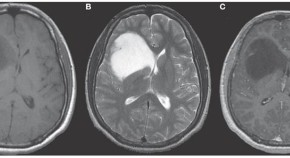

• Baló's concentric sclerosis (BCS) is a demyelinating disorder characterized by white matter lesions consisting of rings of demyelination alternating with rings of relatively intact myelin. In this Review, Mowryet al.discuss how advanced neuroimaging techniques have contributed to our understanding of the pathogenesis of BCS, as well as enabling clinicians to distinguish BCS from other demyelinating disorders such as multiple sclerosis. The authors explore these themes further in a Case Study in this issue.

• Ellen M Mowry

• John H Woo

• Beau M Ances